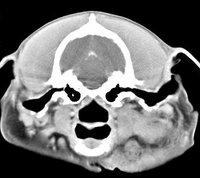

imágenes de TC en el perro | ||||||||||

ejemplo de imágenes de TC en el perro. Nótese la celulitis en la región parotídea izquierda | ||||||||||